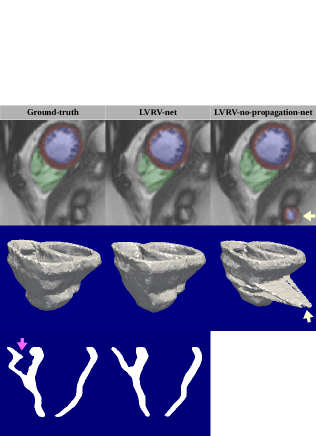

Among the methods in the ACDC challenge, [5] (ranked 1st), [17] (ranked 4th) and [15] (ranked 5th) report their performances on the 100 training cases. The performances on these cases of LV-net and these methods are presented in Table II. Due to the variability of the UK Biobank training set ground-truth, as well as the difference between UK Biobank and ACDC images, LV-net is not as good as the state-of-the-art methods on Dice index. But it is rather comparable to them in terms of the mean of Hausdorff distance, and even better in terms of the standard deviation. This confirms the robustness of our method. In Fig.7(a) we also show some examples of LV-net prediction along with the ACDC ground-truth and the UK Biobank ground-truth on similar slices. It is clear that LV-net learns the segmentation “pattern” of the ground-truth from UK Biobank, which is different from that of ACDC.

IV-C2 Experiments on Sunnybrook

IV-C3 Experiments on RVSC

The slices to be segmented for the 16 cases in RVSC are all located below the base and above the apex. Similar to [3], central zones are cropped out as ROIs. We then apply the trained LVRV-net on these ROIs and evaluate the predicted RVC masks. Comparison with the up-to-date state-of-the-art research is presented in Table V. In terms of Hausdorff distance, our method not only achieves better mean value but also generates much smaller standard deviation value compared the to state-of-the-art. Examples of predicted masks and ground-truth are presented in Fig.7(c).